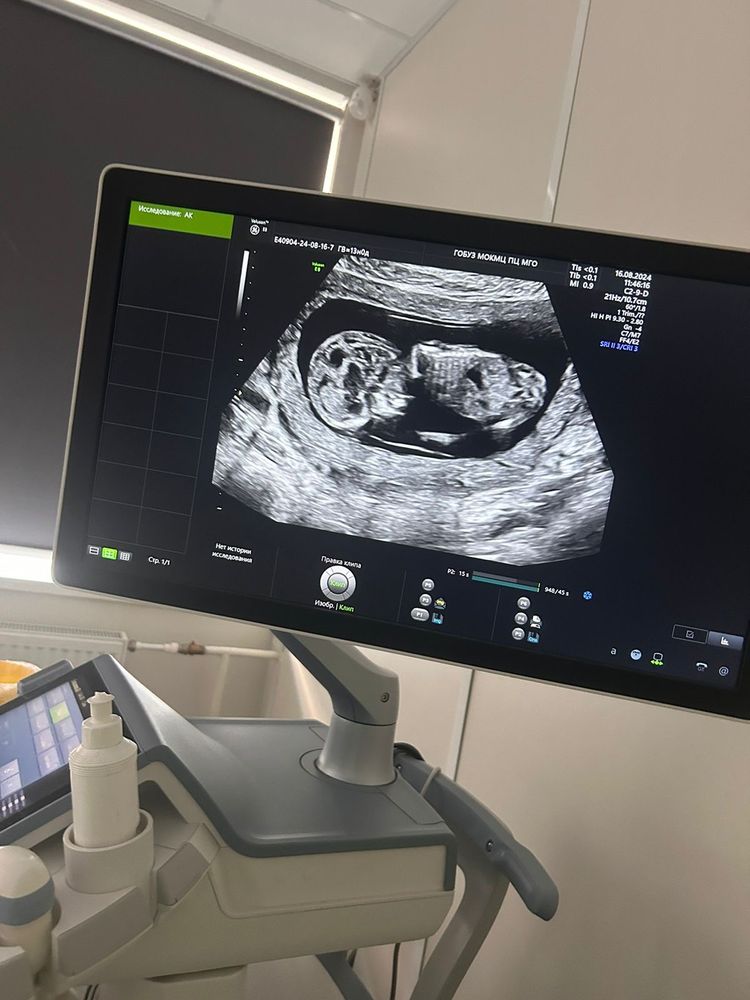

Покажите свои снимки узи 1 скрининга?

Хорошие или плохие не знаю, меня устроили ☺️ Малыша видно.

Но в 15 недель я ходила на УЗИ на хороший аппарат. Мне выдали очень неплохой снимок в 3Д, а вот 2Д совсем неудачный получился.

Малыш согнутый лежал, там даже не сразу понятно, где голова 😅